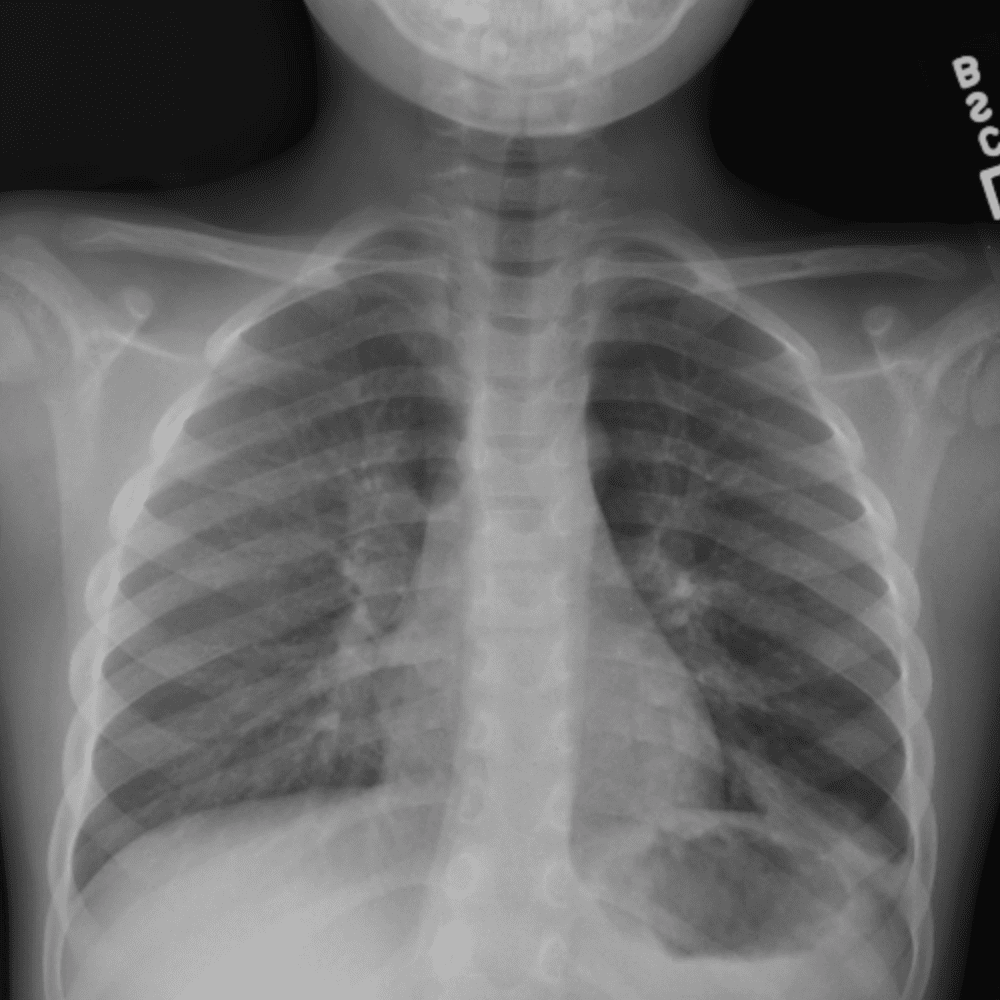

Peds Chest

Practice

Simulates call by including subtle or difficult cases and some normals.

50 cases